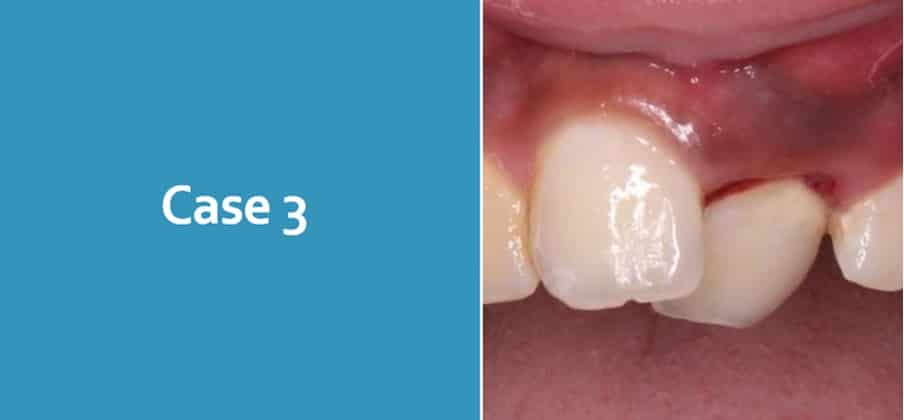

Case 3

12 year old attends with his grandmother following a fall at school 4 days ago. He reports that he is in a lot of pain and is very nervous. Clinical and radiographic examination shows a clear palatal luxation UL1

What are your concerns?

Consent

Attempt to contact parent and document

Act in patients best interest

Patient Gillick competent?

Who has PR? Any social worker involvement?

Delayed presentation?

Who was present at time of injury

Does grandmother look after him often

What is your management?

Full history, clinical and radiographic examination, sensibility testing

Reposition UL1 and splint

Ensure tooth is not interfering with occlusion

Treatment options

LA/RA

Follow up

Ensure patient has follow-up in place

Clinical and radiographic evaluations are necessary: after 2 wk

after 4 wk S+, 8 wk, 12 wk, 6 mo, 1 y, then yearly for at least 5 y

Patients to return if any unfavourable outcomes

Risks:

Resorption

Ankylosis

Loss of tooth

Discolouration of tooth

RCT/Extraction

Interdisciplinary management